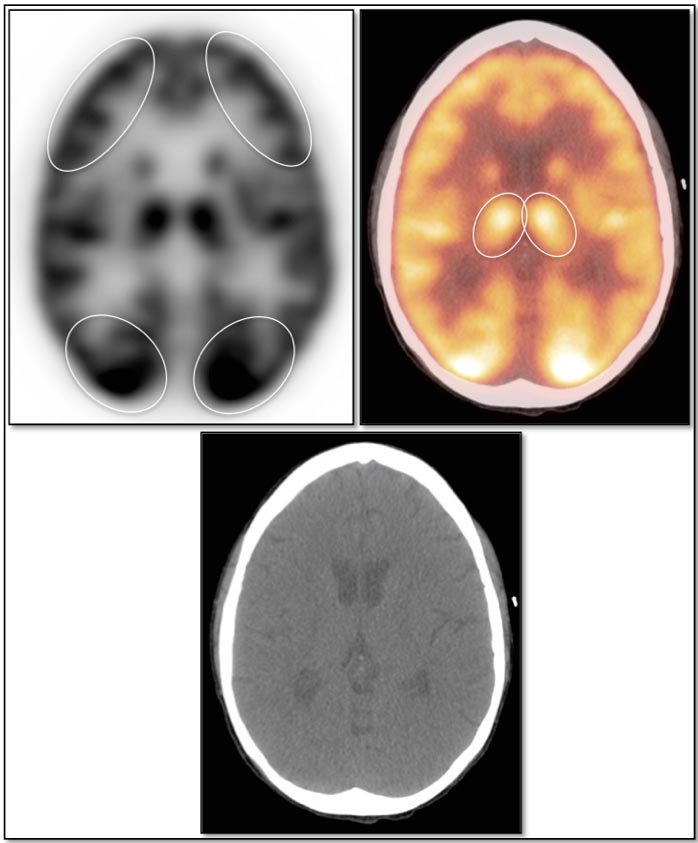

Brain

As the brain fully relies on glucose metabolism, it demonstrates rather diffuse intense uptake of FDG. In fact, its metabolic activity is so intense, that most PET reading software programs will require the reader to manually decrease its intensity to evaluate the brain for potential lesions.

Familiarity with the normal symmetric uptake of FDG in the brain will help the reader identify primary brain tumors and metastatic lesions.

Areas of normal relative increased uptake include the grey matter, basal ganglia, frontal eye fields, posterior cingulate gyrus and visual cortex. Symmetry of uptake should be preserved.